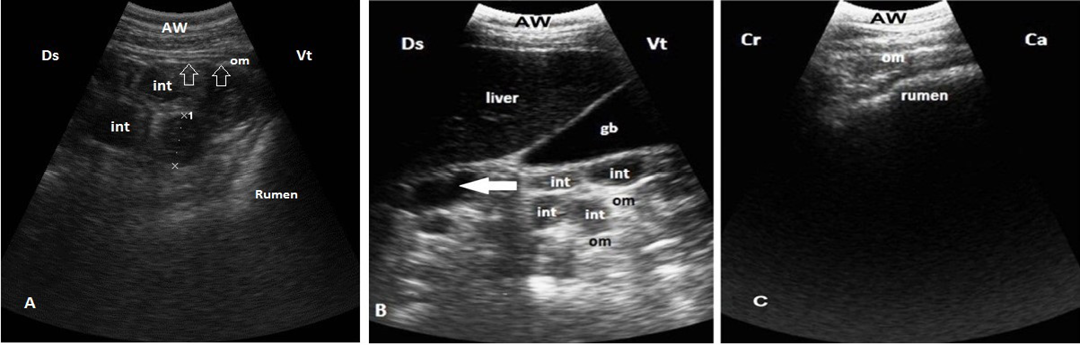

Ultrasonogram shows normal moderate echogenicomentum. A. The intestinal loops (int) are easily visible between rumen and right abdomen from right ventral flank and covered by omentum (arrows). B. Omentum covering the intestinal loops (int) medial to the liver and gallbladder (GB) at 10th ICS, note that duodenum (arrow) not covered by omentum. C.Omentum covers the whole ventral sac of the rumen, imaged from ventral abdomen. Ds: dorsal; Vt: ventral; Cr: cranial; Ca: caudal